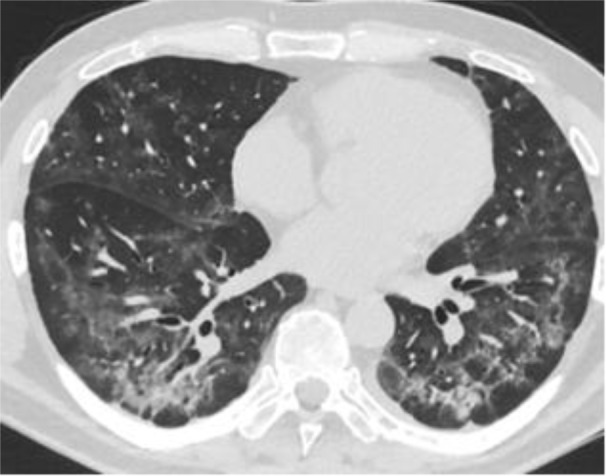

Уникальную эффективность против пневмонии показали ингаляции ксеноном, заявил Лайфу доктор медицинских наук Сергей Наумов. Он рассказал, что в начале пандемии CoViD-19 в декабре 2020 года этот метод применили в ходе лечения 48-летнего пациента с тяжёлой двусторонней вирусной пневмонией. Результатами исследователи поделились в опубликованной научной работе. Вот как выглядели лёгкие до ксеноновой терапии. Видно, что лёгкие в очень плохом состоянии.

Лёгкие пациента до ксеноновой терапии. Фото © National Library of Medicine